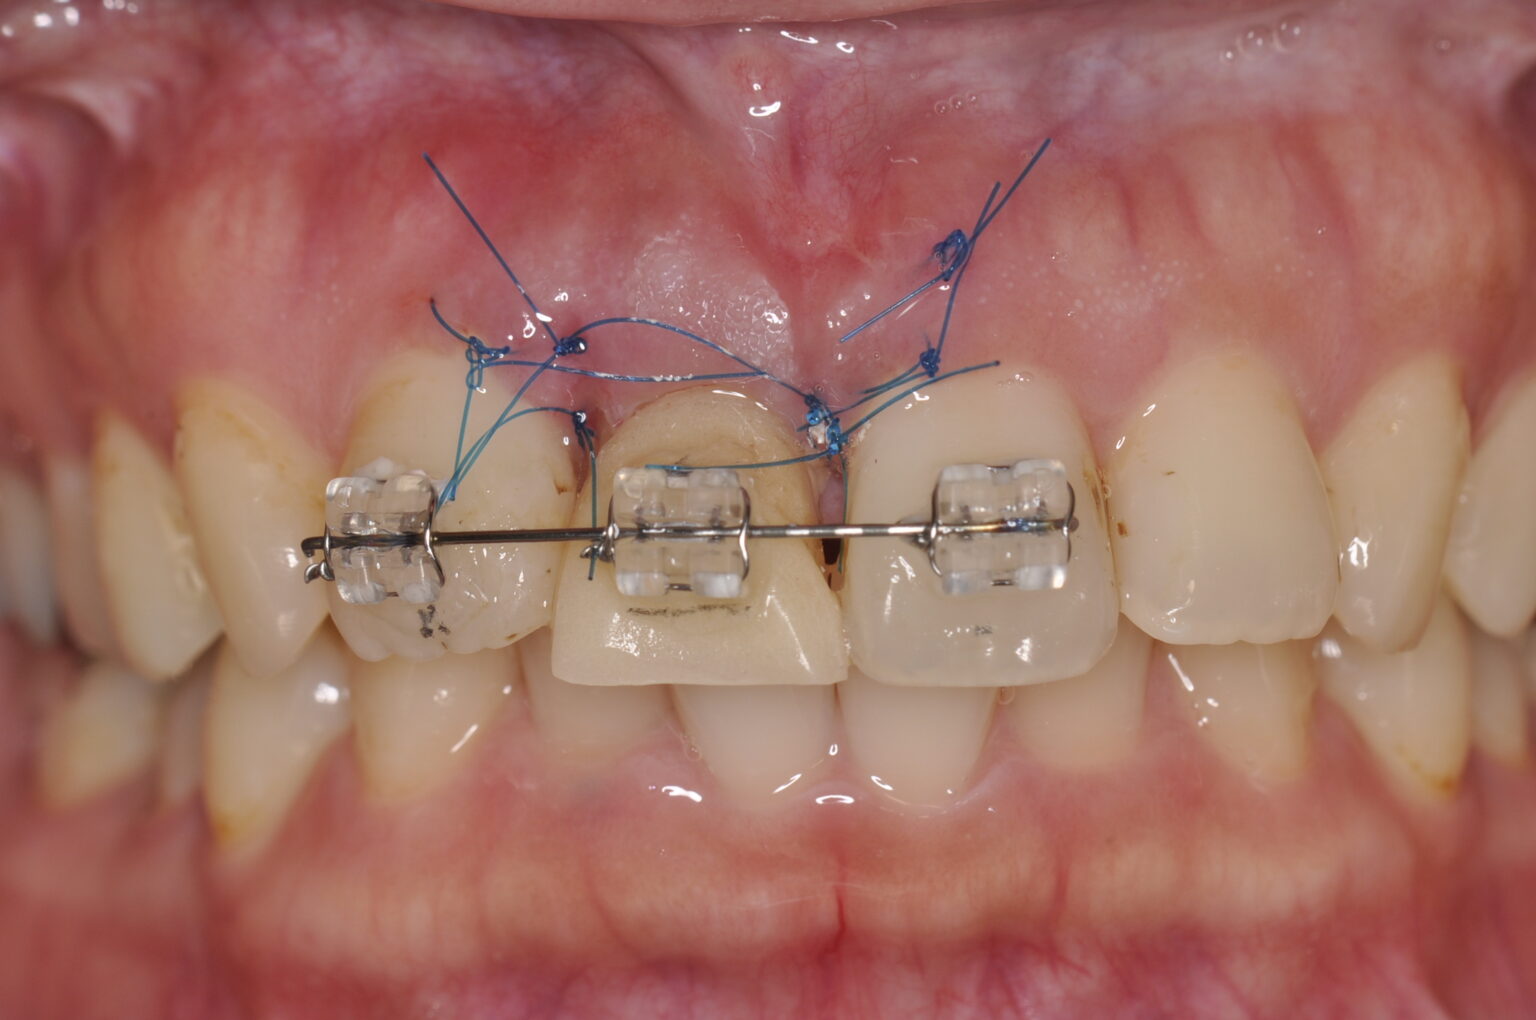

20代女性 歯根破折のためエクストルージョンを行った審美補綴症例

近くの歯科医院に行ったら、抜歯してインプラントですよ。違う方法で治療法がないか相談に来た患者さん

破折線が見えます。

後戻りも考え挺出を

オーバー目に。

症例写真

歯周外科後に保定

歯根破折と言われたが歯を残したい

診断名/主な症状

右上1歯根破折

治療内容

エクストルージョン 挺出

歯周外科

審美補綴治療

使用装置

ブラケット装置

治療期間

6ヶ月

通院回数

10回

費用

25万円